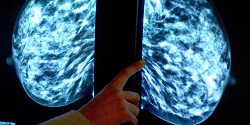

دانشمندان میگویند بعضی از مواد شوینده خانگی، ضد عفونیکنندهها و حشره کشها از جمله عواملی است که میتواند به شکل گیری سرطان تهاجمی سینه در زنان منجر شود.

به گزارش فارس به نقل از یاهونیوز، یافتههای پژوهشگران نشان می دهد قرار گرفتن در معرض مواد شیمیایی موجود در برخی مواد شوینده خانگی، ضد عفونی کننده ها و حشره کش ها خطر شکل گیری سرطان سینه را در زنان افزایش می دهد.

نکته مهم این است که سرطان سینه ای که بدین علت ایجاد می شود، بدخیم بوده و درمان آن نیز مشکل است. پژوهشگران انگلیسی می گویند این نوع مواد شیمیایی عامل شکل گیری 10 تا 20 درصد از کل موارد سرطان سینه در این کشور محسوب می شود.

سرطان سینه ای که بدین شکل ایجاد می شود، در برابر درمان های هورمونی مقاومت زیادی دارد و لذا برای مقابله با آن باید به سرعت از روش هایی همچون عمل جراحی، رادیودرمانی و شیمی درمانی استفاده شود. البته برای درمان موثرتر این نوع سرطان سینه هنوز باید روش های درمانی موثرتری ابداع شود.